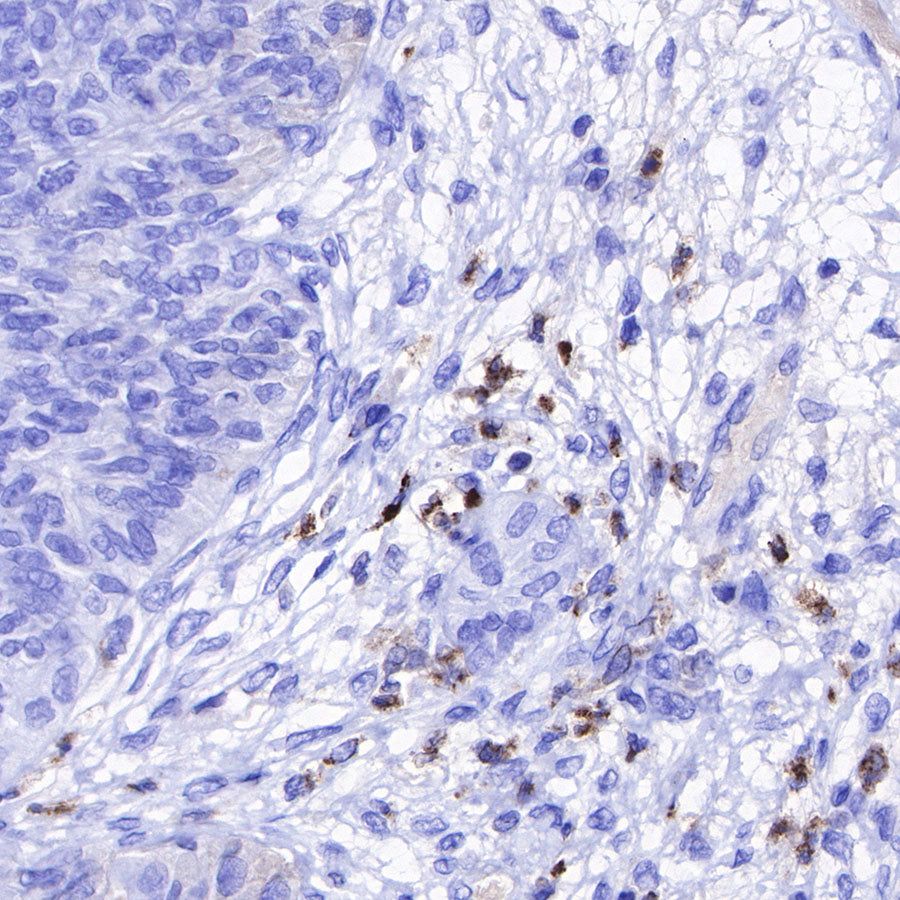

Immunohistochemistry

IHC shows positive staining in paraffin-embedded human colon cancer. Anti-Lysozyme antibody was used at 1/100 dilution, followed by a HRP Polymer for Mouse & Rabbit IgG (ready to use). Counterstained with hematoxylin. Heat mediated antigen retrieval with Tris/EDTA buffer pH9.0 was performed before commencing with IHC staining protocol.

IHC shows positive staining in paraffin-embedded human ovarian cancer. Anti-Lysozyme antibody was used at 1/100 dilution, followed by a HRP Polymer for Mouse & Rabbit IgG (ready to use). Counterstained with hematoxylin. Heat mediated antigen retrieval with Tris/EDTA buffer pH9.0 was performed before commencing with IHC staining protocol.